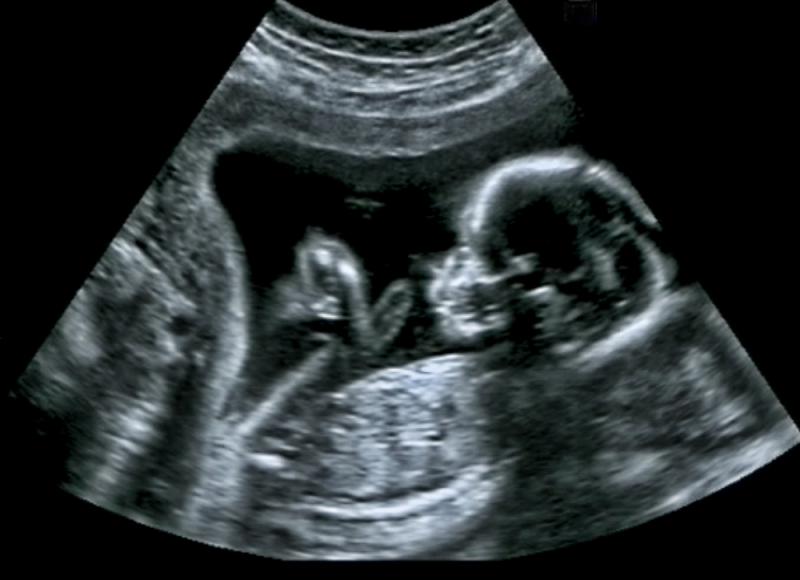

W przypadku ginekologicznego badania USG specjalna głowica jest wprowadzana do pochwy, co umożliwia ocenę stanu szyjki macicy, samej macicy oraz jajników. Badanie wewnętrzne przeprowadzane jest również zazwyczaj w pierwszych tygodniach ciąży – później USG odbywa się już przez powłoki brzuszne. Podczas tego ostatniego położnik ma możliwość oceny ilości zarodków, pomiaru wielkości płodu i bicia jego serca, lokalizacji płodu i łożyska, pomiaru przezierności karkowej (ważnego kryterium diagnostycznego w kontekście zespołu Downa), a także ewentualnych nieprawidłowości rozwojowych. Na podstawie badania USG określa się dziś termin porodu.